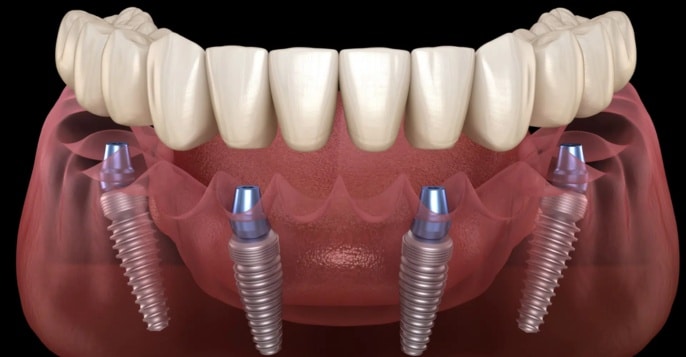

All on 4 dental implants is a procedure involving four implants strategically placed in the jaw that can support the entire replacement of teeth. It is a modern solution that fully restores either the upper or the lower arch using as few as four implants for a very strong and stable support to a fixed dental prosthetic. Using fewer implants greatly decreases the need for bone grafting compared with traditional implant solutions, thus making this procedure more efficient and more economical for the patient.

All on 4 dental implants are placed in a manner such that they can be angled appropriately in order to maximize bone support, which means they often circumvent areas of low bone density and therefore minimize or even avoid the need for bone grafts.

All on 4 dental implants support the entire arch and then allow pressure distribution, further giving way to comfort and proper function. Such stability allows for patients to bear a natural bite force and diet with considerable variety.